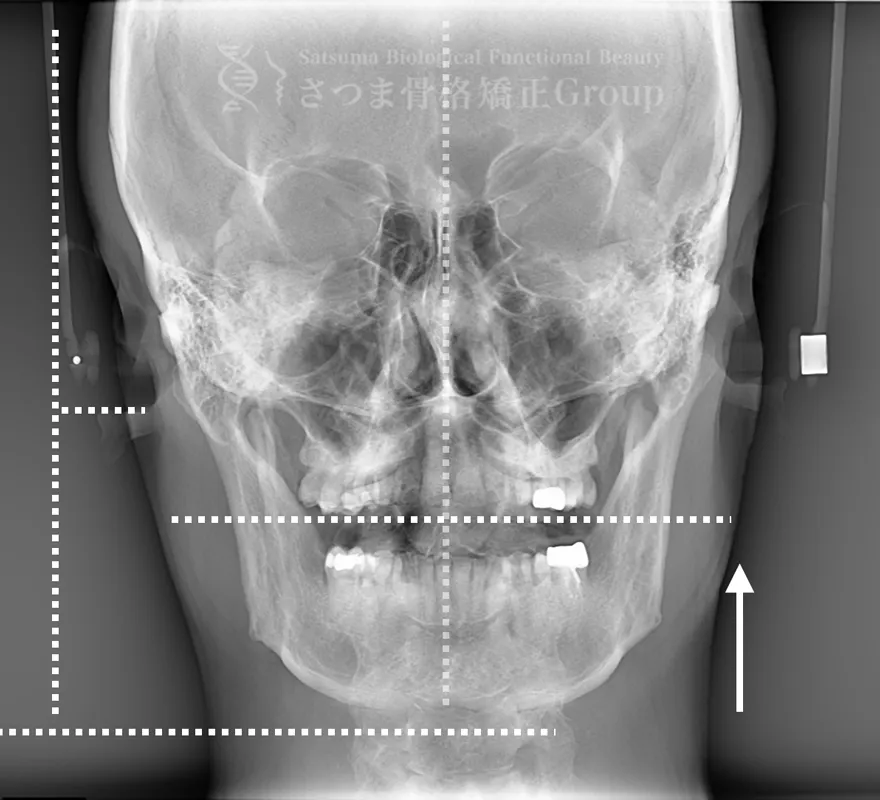

BEFORE

軽度の顎変形症あり

下顎の左方シフト

頚椎の斜頸

中顔面の滑落

Mild jaw deformity present

Leftward shift of the mandible

Cervical spine torticollis

Sagging of the midface

AFTER

下顎の正中誘導

頚椎の斜頸矯正

中顔面の短縮

Midline correction of the mandible

Correction of cervical spine torticollis

Shortening of the midface